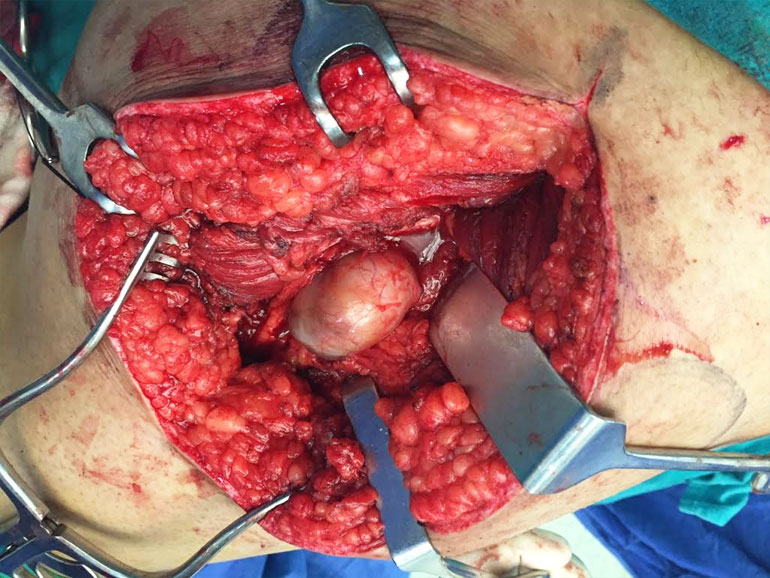

15yrs old girl with large sciatic nerve tumor wondering since 1yr in Jaipur, open biopsy was done elsewhere diagnosed as neurofibromas and she land up with infected bad biopsy scar with discharging sinus

I operated her 5days back with complete removal of tumor along with biopsy scar and track with dissecting nerve fibers from mass and now she has no neurological deficits and full range of movements of knee and foot

19yr old boy schwannoma sciatic nerve at level of LT with no neurological deficit, operated 3 months before by microscopic disection of nerves fibres and tumour removed en bloc. Post op no neurological deficit, pt return to his work after 15 days, at 3 month pt has no complaints leading normal life.